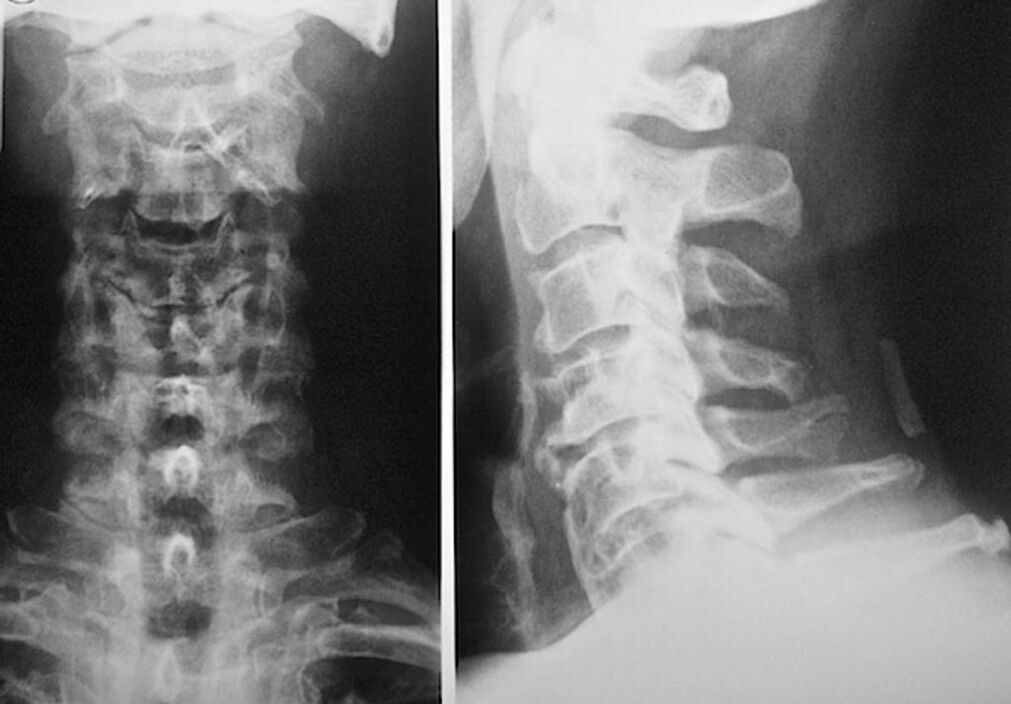

За диагностициране и точна оценка на състоянието на междупрешленните дискове се използват следните методи на изследване:

- Рентгенография.

- CT сканиране.

- Магнитна томография.

- Ултразвуково сканиране на съдовете на шията.

Всеки от тях е напълно безопасен за здравето и не носи заплаха от прекомерно излагане. Диагностицирането на остеохондроза на шийните прешлени, чието лечение ще се извършва през останалата част от живота, може да се извърши след прост визуален преглед. Всеки ортопед може лесно да направи това. Изключение е първият стадий на заболяването, когато не се забелязват видими патологии на цервикалната област.